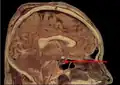

Расположение гипофиза в человеческом мозге

Гипофиз на сагиттальном и корональном срезах МРТ с контрастным усилением